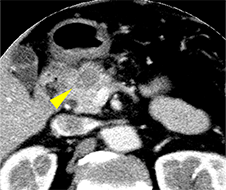

CTで膵頭部腫瘤を指摘

EUS-FNAで組織採取

採取された検体

膵癌と診断